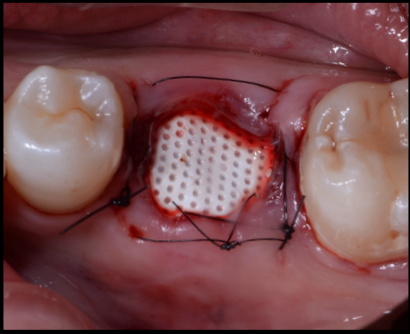

| 治療内容 | 極度の歯科恐怖症で、無痛リラクゼーション治療を希望。 1ヶ月後にカナダに帰るとのことより、それまでに治療を終えてほしい。 左下奥歯は破折を認め、保存が困難な状況であった。他にも治療途中の歯があり、左奥歯がなくなると食事に困るとのことよりブリッジ治療を選択。 本来であれば、抜歯後5ヶ月ぐらいは待つが歯周組織の変化をコントロールするためにソケットプリザベーションと歯肉縁下形成を併用し、即日印象、プロビジョナルレストレーションを調整し、次回アポイント時セットを行なった。 |